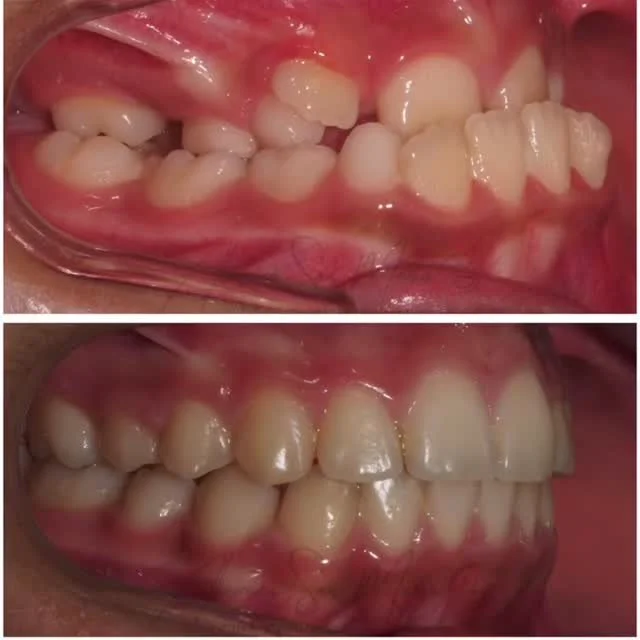

En la Clínica Alamán San Martín todos los tratamientos de Ortodoncia los realiza un Especialista Universitario en Ortodoncia, siempre tras un estudio diagnóstico en profundidad con la exploración clínica y valoración de todos los registros necesarios según la complejidad de cada paciente.

Actualmente la Ortodoncia se realiza a cualquier edad para mejorar la salud bucal, la función masticatoria y la estética, al conseguir un buen alineamiento de los dientes y una relación ósea intermaxilar adecuada con una oclusión normal, por lo que recomendamos hacer una revisión de ortodoncia por lo menos desde los 6 años de edad si no se detecta nada antes.

En Clínica Alamán San Martín ofrecemos diversos tratamientos de ortodoncia como: Ortodoncia infantil y adultos, Ortodoncia Estética, Ortodoncia Transparente con Alineadores, y Ortodoncia quirúrgica para Cirugía ortognática.